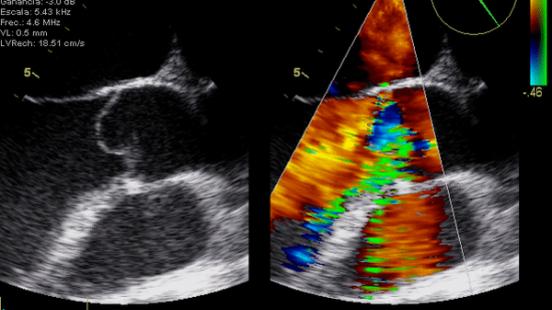

Gràcies a l’ús d’ultrasons, l’ecocardiografia permet estudiar la mida, el funcionament i els moviments del cor. Aquesta és la tècnica diagnòstica més utilitzada en cardiologia. Malgrat que els cardiòlegs són els professionals sanitaris que millor dominen aquest procediment, hi ha altres professionals que també necessiten conèixer com funciona. Com explica el Dr. Artur Evangelista, director del Curs Teòric-pràctic d’Ecocardiografia Bàsica i d’Ecocardiografia Avançada en Medicina Intensiva, Anestèsia i Reanimació, “metges de família, internistes o neuròlegs també necessiten realitzar ecocardiografies per tractar els seus pacients”. D’aquesta manera, el Curs Teòric-pràctic d’Ecocardiografia Bàsica i d’Ecocardiografia Avançada en Medicina Intensiva, Anestèsia i Reanimació consta de dues parts. “Una primera part de coneixements bàsics perquè aquests professionals, i també els cardiòlegs que estan començant, puguin realitzar ecocardiografies i detectar possibles problemes. L’ecocardiografia et dóna imatges de com està el cor, però aquestes imatges, és clar, s’han de saber interpretar, que és el que ensenyem en aquest curs —assenyala el Dr. Artur Evangelista—. Si aquests professionals detecten alguna possible patologia, després poden derivar el pacient al cardiòleg, que és l’especialista”.

El curs ha combinat seminaris teòrics i tallers pràctics per mostrar, entre altres aspectes, les bases de l’ecocardiografia i l’anatomia ecocardiogràfica, l’optimizació de l’ecocardiògraf, el Doppler cardíac, l’ús de l’ecocardiografia en el shock, el dolor toràcic agut, la síndrome coronària aguda, la insuficiència cardíaca, el preoperatori, l’ecocardiografia transesofàgica o l’ecografia pulmonar. Un dels aspectes més destacats ha estat l’ús de simuladors, per tal d’apropar la formació a les situacions reals de pràctica clínica que es poden trobar els professionals. Els simuladors augmenten la destresa en l'estudi i la interpretació de les imatges i permeten analitzar un ampli nombre de patologies. Aquesta eina s'ha convertit en un element imprescindible en la formació teòric-pràctica en ecocardiografia.